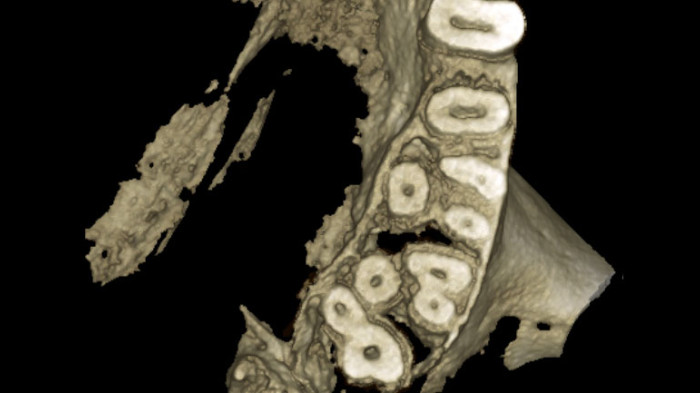

Szkolenie ma na celu przedstawienie możliwości analizy skanów CBCT w przypadku tych oraz innych gałęzi stomatologicznych. Przy wykorzystaniu odpowiednich funkcji w dedykowanym oprogramowaniu możemy zapoznać się z budową anatomiczną zęba leczonego endodontycznie, bądź sprawdzić jakość takiego leczenia, jeśli odbyło się ono w przeszłości.

Możliwości oraz ograniczenia obrazowania 2D i 3D – kiedy i jakie badanie należy zlecić pamiętając o zasadzie ALARA. Jakość badania RTG – co na nią wpływa, jak ją oceniać, jak wyeliminować potencjalne błędy rzutujące na obniżenie jakości badań radiologicznych. Poruszanie się po badaniu CBCT – możliwości oceny tkanek oraz stanów patologicznych poprzez wyświetlanie badania w formie przekroi, rekonstrukcji wolumetrycznej, rekonstrukcji badań 2D (MPR – multi planar reconstruction). Mnogość narzędzi w oprogramowaniu KaVo RTG – jak efektywnie wykorzystywać je na co dzień w poszczególnych przypadkach z zakresu chirurgii, endodoncji, ortodoncji, etc.

Podczas tego praktycznego wydarzenia wspólnie odkryjemy, jak zaawansowane technologie obrazowania rewolucjonizują współcześnie diagnostykę. Razem zgłębimy strategie efektywnego wykorzystania różnych technik diagnostycznych, takich jak tomografia komputerowa i zdjęcia rentgenowskie, w celu precyzyjnej oceny stanu tkanek zęba oraz korzeni. Dokonamy także analizy obrazów i pokażemy, jak dokładne diagnozy mogą wpłynąć na skuteczność leczenia endodontycznego.

• diagnostyką anatomii zębów kwalifikowanych do leczenia endodontycznego,

• możliwościami lokalizacji złamań, pęknięć oraz perforacji w badaniach obrazowych,

• diagnostyką zmian OKW,

• prawidłowym dokonywaniem pomiarów w obrębie badań CBCT,